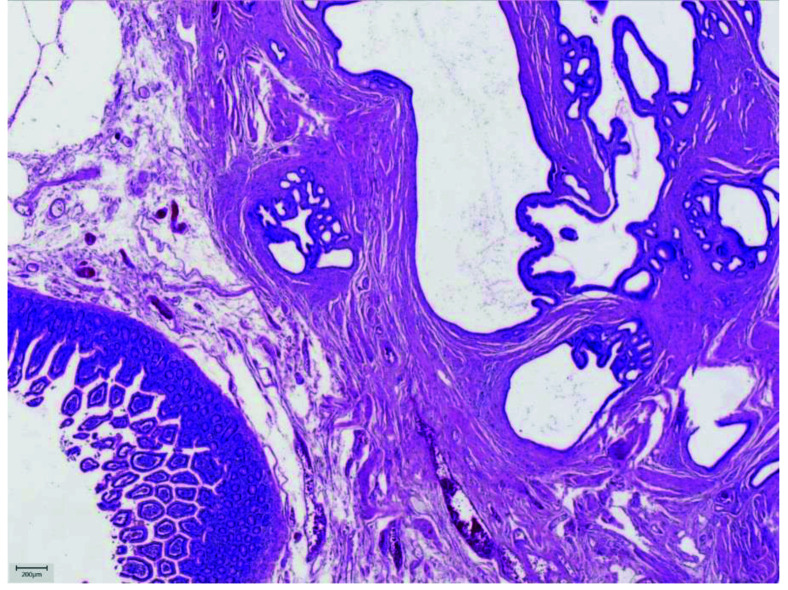

Pancreatic heterotopia is a relatively rare condition that implies pancreatic tissue anatomically separated from the main gland, showing no vascular or ductal continuity. It is known to occur in many sites of gastrointestinal tract, with stomach being the most common one. This case is of great interest because ectopic pancreatic tissue in jejunal wall presented as bowel obstruction. The aim of this article is to provide a review of clinical, histopathologic and immunohistochemical features of ectopic pancreatic tissue in jejunum, emphasizing the possible diagnostic pitfalls in gastrointestinal tract, especially in its upper parts. Knowing the most common locations, imaging features and histopathologic criteria, the diagnosis of pancreatic heterotopia could be successfully set preoperatively. Associated complications are various and sometimes difficult to handle, so accurate and precise diagnosis, as well as surgical resection, is often needed.

Abstract Image